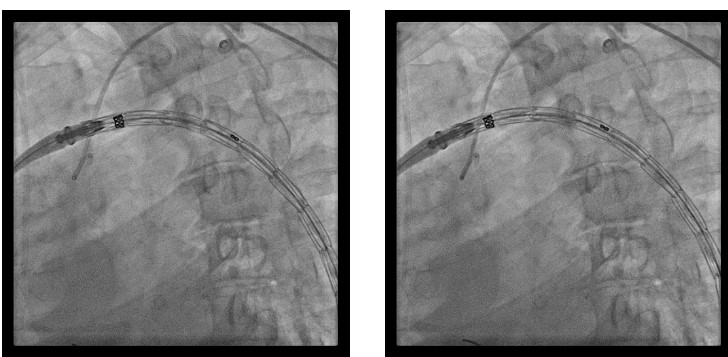

A pigtail catheter was kept in the arch of the aorta for land mark. A guidewire was taken. Then the stent graft was positioned. 32x204 Valiant Thoracic Stent was chosen. It was placed in descending thoracic aorta from arch of the aorta just distal to left subclavian artery covering ruptured dissecting flap atthoracic aorta. After deployment, final aortogram showed ruptured segment of aortic dissection completely sealed with well visualised rest of the thoracic and abdominal aortaand its bifurcation to the lower limb arteries.